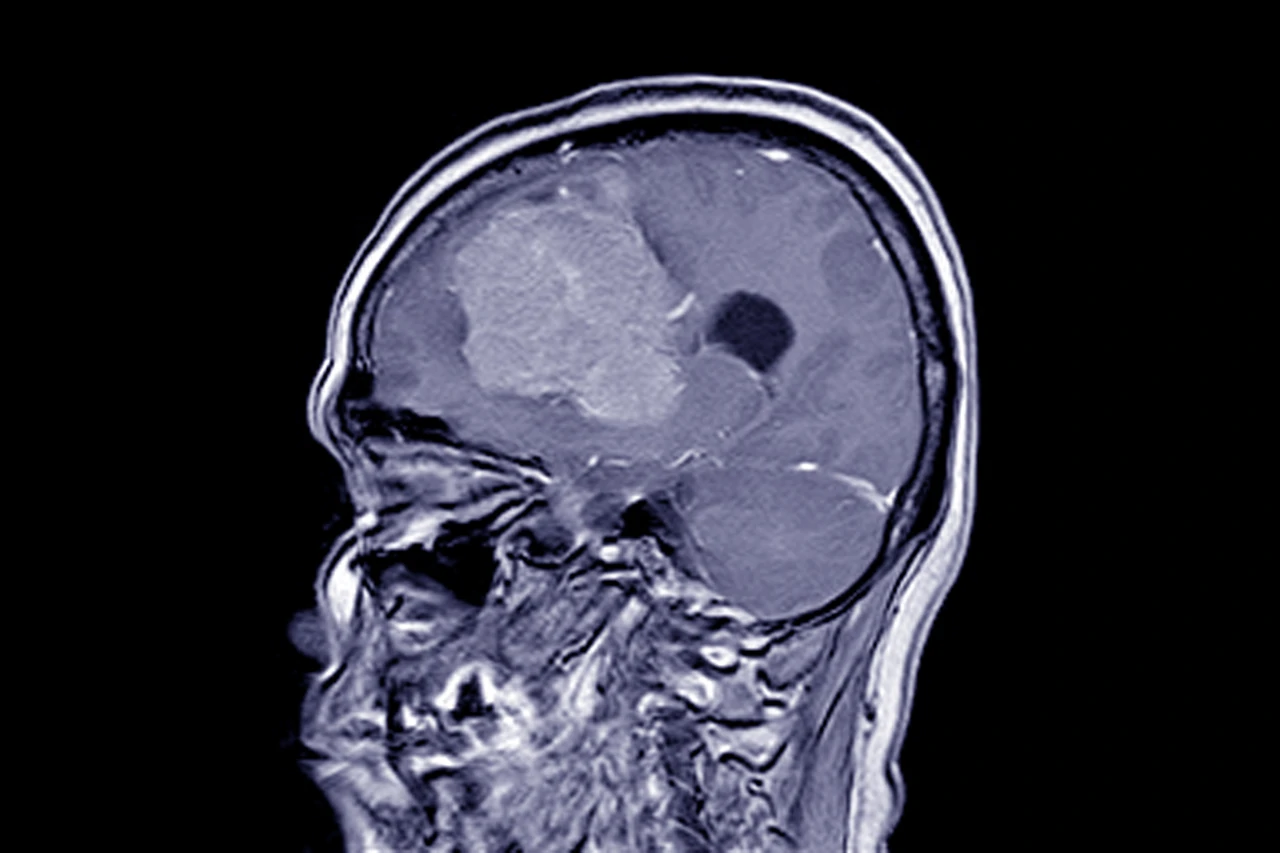

Менінгіома — це пухлина, що розвивається з оболонок головного мозку. Вона може бути доброякісною або злоякісною, але навіть у разі успішного видалення пацієнта чекає непростий період відновлення. Багато хто цікавиться, скільки триває реабілітація після такої операції і які етапи вона включає. Детальніше про це, а також про можливі наслідки після хірургічного втручання, можна дізнатися на сайті — https://time.org.ua/naslidky-pislya-vydalennya-meningiomy/.

У середньому, реабілітація після операції триває від кількох тижнів до року. У деяких випадках процес відновлення може затягнутися на кілька років, якщо були уражені важливі зони мозку, відповідальні за рух, мову чи зір.